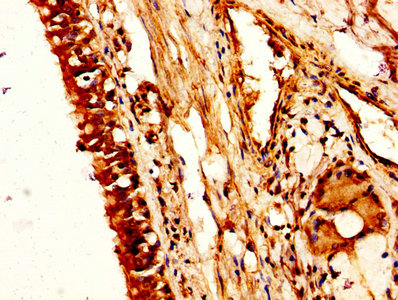

IHC image of CSB-PA016146HA01HU diluted at 1:200 and staining in paraffin-embedded human lung cancer performed on a Leica BondTM system. After dewaxing and hydration, antigen retrieval was mediated by high pressure in a citrate buffer (pH 6.0). Section was blocked with 10% normal goat serum 30min at RT. Then primary antibody (1% BSA) was incubated at 4°C overnight. The primary is detected by a biotinylated secondary antibody and visualized using an HRP conjugated SP system.